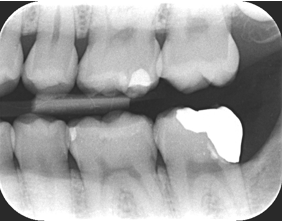

主訴:親知らずが気になる

Before

通院時の年齢 | 44歳 |

---|---|

性別 | 女性 |

通院回数 | 20回程度 8ヶ月 |

通院目的 | 自分の歯を残したい |

処置内容 | アップライト矯正治療 |

費用 | 10万(歯周病治療は保険治療・被せ物は自費診療で今回の費用には含まない) |

デメリット・注意点 | 歯周病にかかっている患者さんは矯正治療を受けられない可能性があります 歯周病にかかっている歯は歯周病の治療が完了してから矯正の可否を判断します うまく矯正治療で動かない場合があります |

備考 | 抜歯になると入れ歯かインプラントを選択しなくてはならず費用は3倍近くかかります 保険の入れ歯は咬むことを阻害してしまうので身体への害はもちろんのことせっかく治療した歯の歯茎がすぐに下がって再度虫歯になってしまう可能性や引っかけの歯に負担が大きくなり抜歯になることがあります |